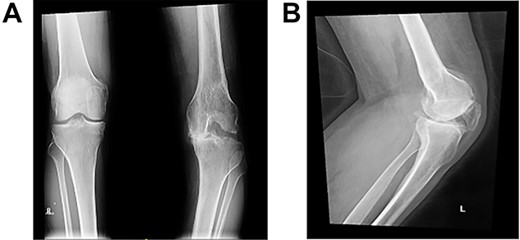

Post-operative plain radiographs from follow-up visits; (A) 3-month post-operative AP radiograph showing implant in place with a lateral gap sized to be 3.2 cm; (B) 3-month post-operative lateral radiograph of the knee showing implant in a satisfactory position.